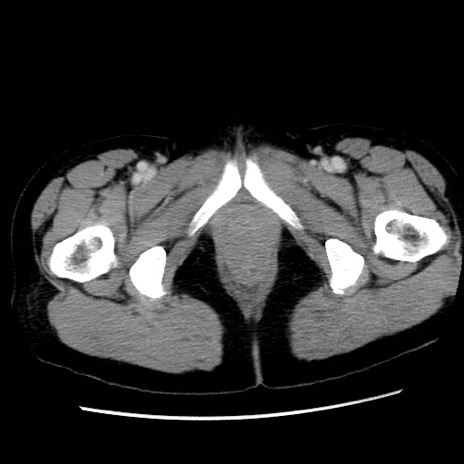

症例10(横断像)

【症例】 50歳代女性

【主訴】 腹痛

【現病歴】前日生レバーを食べた。今朝に排便あり。 昼前に突然発症の腹痛を生じ、当院救急外来を受診した。

【身体所見】 意識清明、腹部:平坦、軟、下腹部やや左を中心に圧痛・反跳痛あり、筋性防御あり

【データ】WBC 7800、CRP 0.07